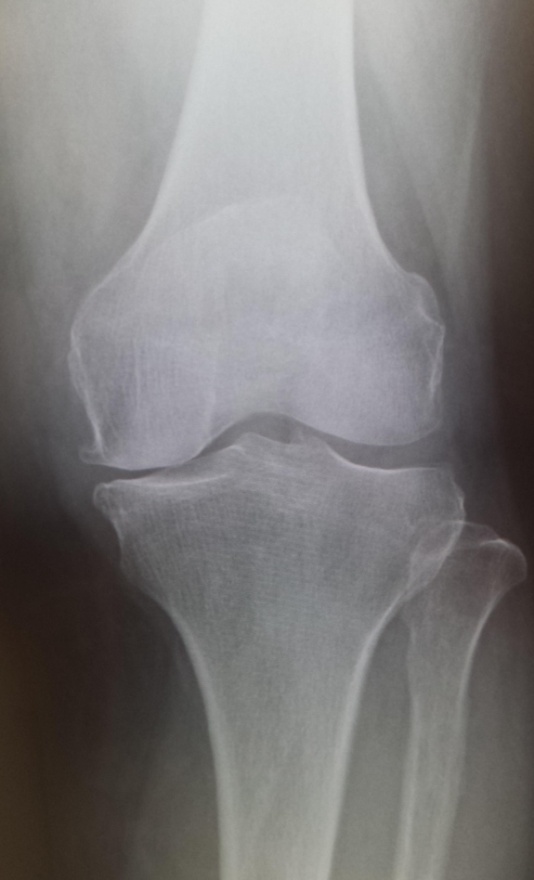

当院でおこなった高位脛骨骨切り術

手術前